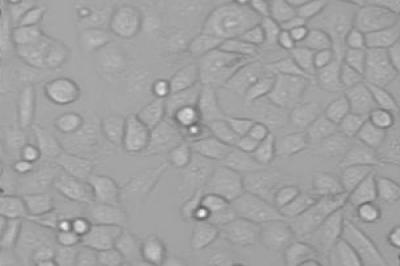

Scientists used cells taken from human tumours and looked at the effect of blocking each of these two energy sources in turn.

Their study, funded by the Biotechnology and Biological Sciences Research Council (BBSRC), Central Manchester University Hospitals NHS Foundation Trust (CMFT)/National Institute of Health Research (NIHR) Manchester Biomedical Research Centre and AstraZeneca, shows that blocking mitochondrial metabolism had no effect. However, when they blocked glycolysis, they saw a reduced supply of ATP which inhibited the calcium pump, resulting in a toxic calcium overload and ultimately cell death.